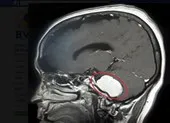

Khối u não của bệnh nhân lớn bằng quả bóng golf hình thành từ tế bào mầm được tạo ra từ khi phôi phát triển trong tử cung. Các bác sĩ cho biết, thông thường tế bào mầm này phát triển thành tinh trùng hoặc trứng (tùy giới tính của thai nhi).

Khối u hiếm của anh Payne vừa được phát hiện vào cuối tháng 3-2018 khi anh đột nhiên tăng cân, mắc chứng lẫn lộn, không thể nhớ được tên bạn bè. Trước đó, trong khi đang làm việc ở công trường xây dựng, anh bị một viên đá từ đường ống bể bay trúng mũ bảo hiểm. Tuy không bị thương nhưng anh vẫn được bạn bè khuyến khích đi chụp CT. Và từ đó, khối u gây ung thư não được phát hiện ra.

Mặc dù đã được trị liệu, nhưng khối u của anh vẫn phát triển. Hy vọng duy nhất của anh lúc này là 1 cuộc phẫu thuật não nhiều nguy cơ, có thể khiến anh tử vong hoặc mù hay liệt vĩnh viễn.

Trong tử cung, dương vật của thai nhi là thứ hình thành sau cùng. Tế bào tạo ra nó di chuyển từ não qua cột sống tới vùng sinh thực. Trong trường hợp của anh Payne, không phải hầu hết các tế bào mầm này rời khỏi não, chúng đã ở lại não nhiều năm liền, trở thành khối u ung thư.